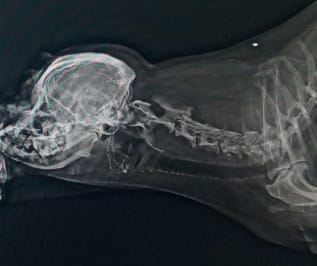

Omurga Kırığı ve Fıtığı Nöroşirurji Ameliyatları

Ortopedi Cerrahi